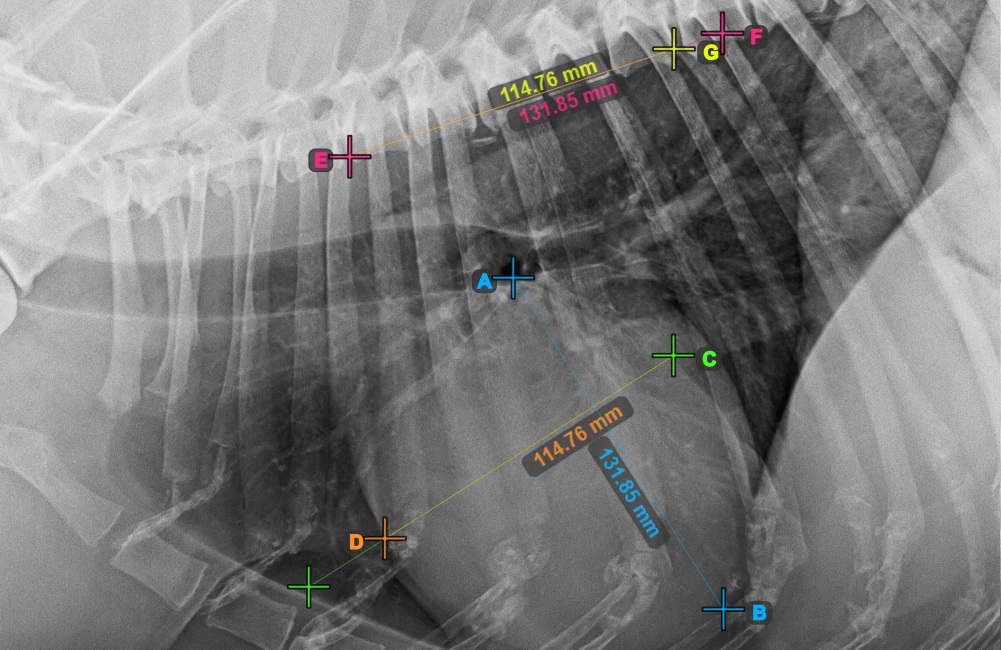

Azonosítsa a T4 csigolya kezdetét (a gerinc negyedik csigolyatestét), a gerinc kezdőpontjától számítva. Jelölje meg a T4 csigolya kezdetét a mérés folytatásához. A szoftver a megjelölt pontból vonalakat húz a gerinc mentén. A vonalak hossza a szív mért hossz- és rövidtengelyétől függ.

Az alábbi kép a gerinc negyedik csigolyatestének kezdetén lévő pont tipikus elhelyezkedését mutatja.

A szükséges VHS-kalkulációk elvégzése előtt győződjön meg róla, hogy a vonalak pontosan a csigolyák mentén helyezkednek el.